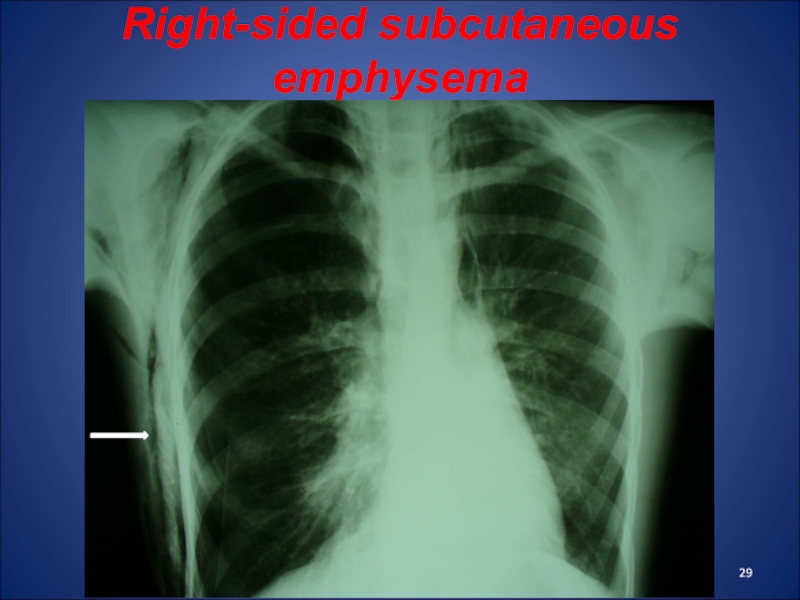

Слайд 28Subcutaneous emphysema

Clinic: in palpation of the affected area is defined symptom crepitation. In severe cases, emphysema is distributed on the neck, back and lumbar region. Patient recalls hyped rubber toy. There dyspnea, cyanosis, tachycardia.

Treatment: rest, painkillers, antitussives. With progressive emphysema must spend puncture or skin incisions with drainage of emphysema cavity.

Слайд 29Right-sided subcutaneous emphysema

Right-sided subcutaneous emphysema